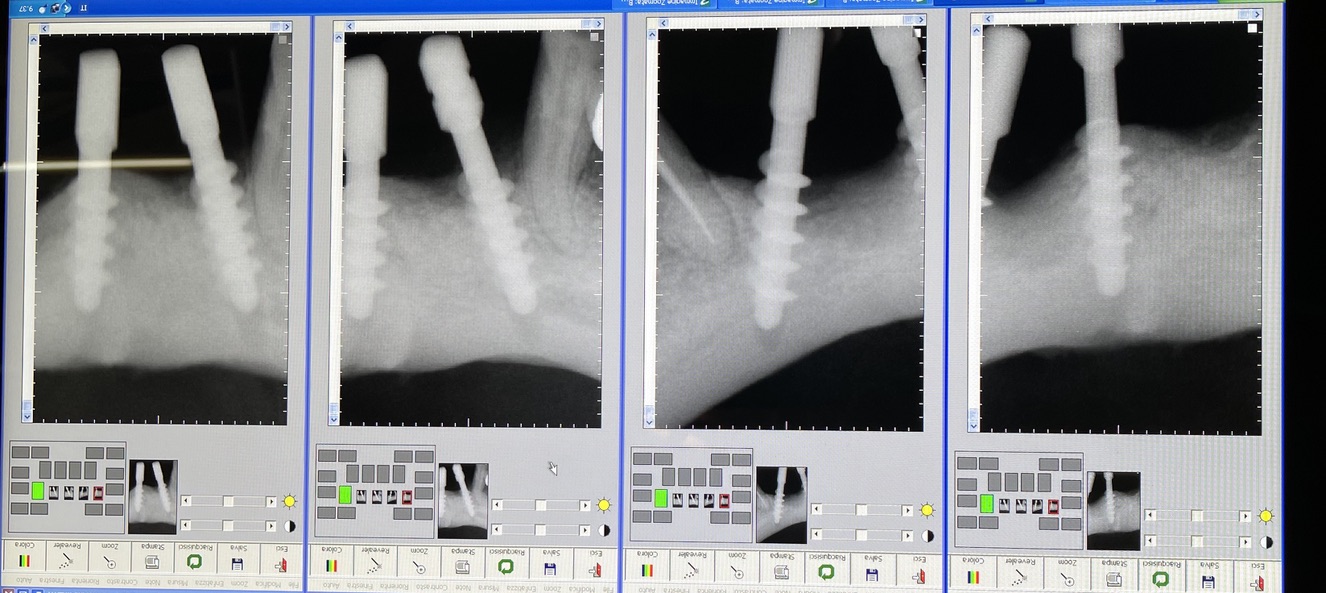

CLINICAL CASE combined with news n.6. Rehabilitation of 04/28/2021

In particular, I consider the following aspects to be significant:

• 12 Implant failure of lower Tramonte implant, implant prior to 2004, in the context of general periodontal disease

• 13 The insertion of the three implants did not involve bone or connective tissue grafts

• 14 It did not make detachments necessary

• 15 It was not necessary to isolate the emergencies of the inferior alveolar nerves

• 16 Since we are dealing with high-density bone, we resorted to the helical drill, an instrument rarely used by us because it is not necessary and because there are areas where its use involves surgical risks that are not acceptable to us. In addition, this drill removes discrete amounts of bone that we prefer to remain where nature has put it. It is interesting that the diameter of the cutter is only 2 mm

• 17 Being dense bone, the implants used had a diameter of only 4 mm after tapping with the corresponding tap

The images provide additional information in the captions.